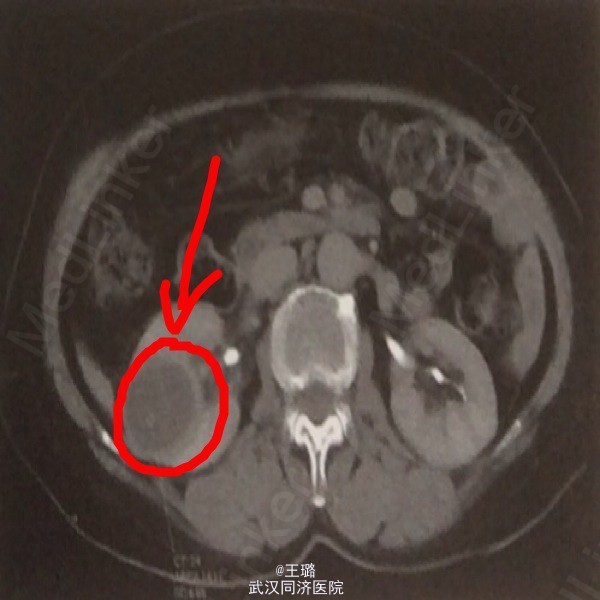

患者,女,65岁 因“右腰痛伴间断性肉眼血尿10余天”入院,患者10天前出现阵发性腰痛,可自行缓解,疼痛发作时伴有发热。晨起小便血色。

体检:面色贫血貌,肾区叩诊阳性,余为阴性。实验室检查:血常规:白细胞正常,红细胞降低,Hb:105;血生化:肌酸增高,白蛋白降低。血沉增快。电解质:钙离子升高。影像学检查:IVP示:右肾上盏稍有扩张,小盏杯口变圆钝。CT平扫示右肾中部类圆形低密度影,边界欠清。

诊断:右肾炎肌纤维母细胞瘤(术后病理) 治疗:腹腔镜下手术切除占位灶,术后给予肾炎常规激素治疗。